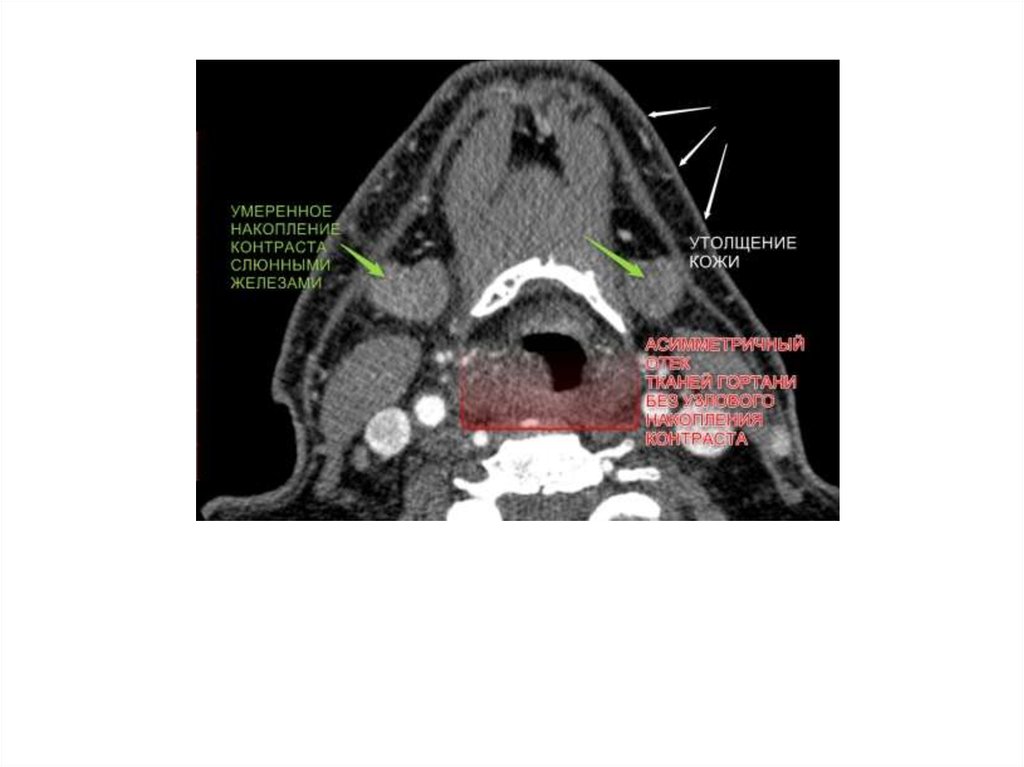

19. Примеры патологии

2. Пациент А., 16 лет

• Диагноз: Острый стенозирующий

ларинготрахеит. Стеноз гортани 3 степени.

• An. morbi: ухудшение состояние в течение

2 дней, когда появился лаящий кашель.

Постепенно симптомы прогрессировали:

температура, звучность голоса пропала. В

связи с ухудшением состояний пациент

был доставлен в ЛОР клинику.